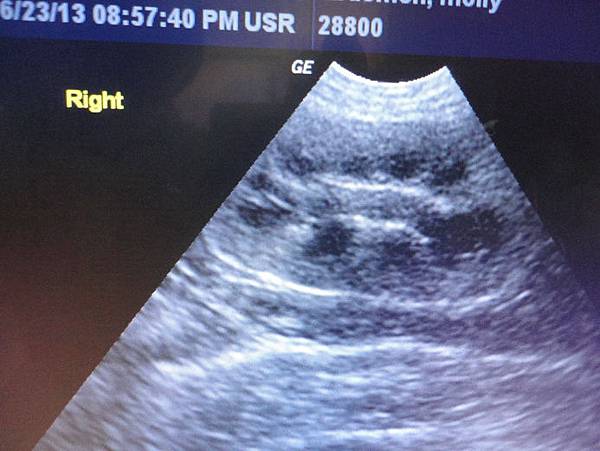

再看了腎臟

大致上還正常,但有老化的跡象